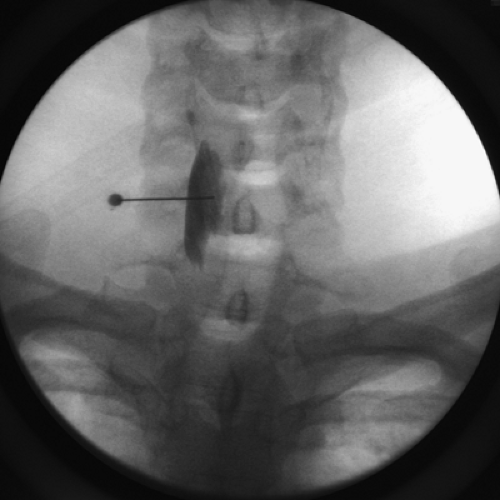

The doctor will also apply some pressure on your neck to determine exactly where to place the needle. It is very important that you do not talk, swallow, or cough. If you have to swallow or cough, raise your hand to let someone know. After the numbing medicine takes effect the doctor will insert another needle, and with the assistance of a special X-ray machine called a fluoroscope, inject a radiopaque dye (contrast solution) to confirm correct needle position. When satisfied with the needle position, the doctor will inject a small mixture of numbing medicine (anesthetic) and anti-inflammatory medicine (cortisone/steroid). Although it takes about 10 to 20 minutes for the medication to take effect, you will remain at the Clinic until the doctor feels you are ready to leave.